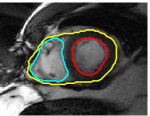

The problem above is a generalization of Horn & Schunck optical flow. Note that solving for the Horn & Schunck optical flow within each region separately does not lead to motions such that at the interface, they have equal normal components (see Figure 1), whereas the solution of (5) to be presented in subsequent sections does. Note that computing Horn & Schunck optical flow in each region requires boundary conditions (and typically they are chosen to be Neumann boundary conditions: and on ). Note that replacing these boundary conditions with the boundary constraint (6) does not specify a unique solution. Also, while Horn & Schunck optical flow computed on the whole domain naturally gives a globally smooth motion, which by default satisfies matching normals at the interface, this is not natural for the ventricles / myocardium, where different motions exist in the regions (see Figure 2), and the motions should not be smoothed across the regions.

![]() |

| image + boundary | next image | within region optical flow | our method |